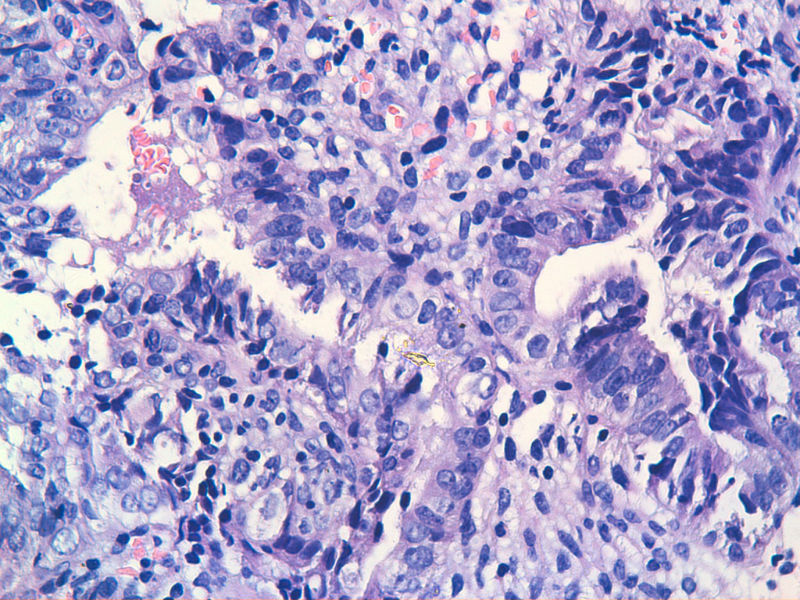

图13是做为正常对照的,图7、8、9、12显示的核大小不一,空泡状,形状不规则。女,48岁,宫血半年